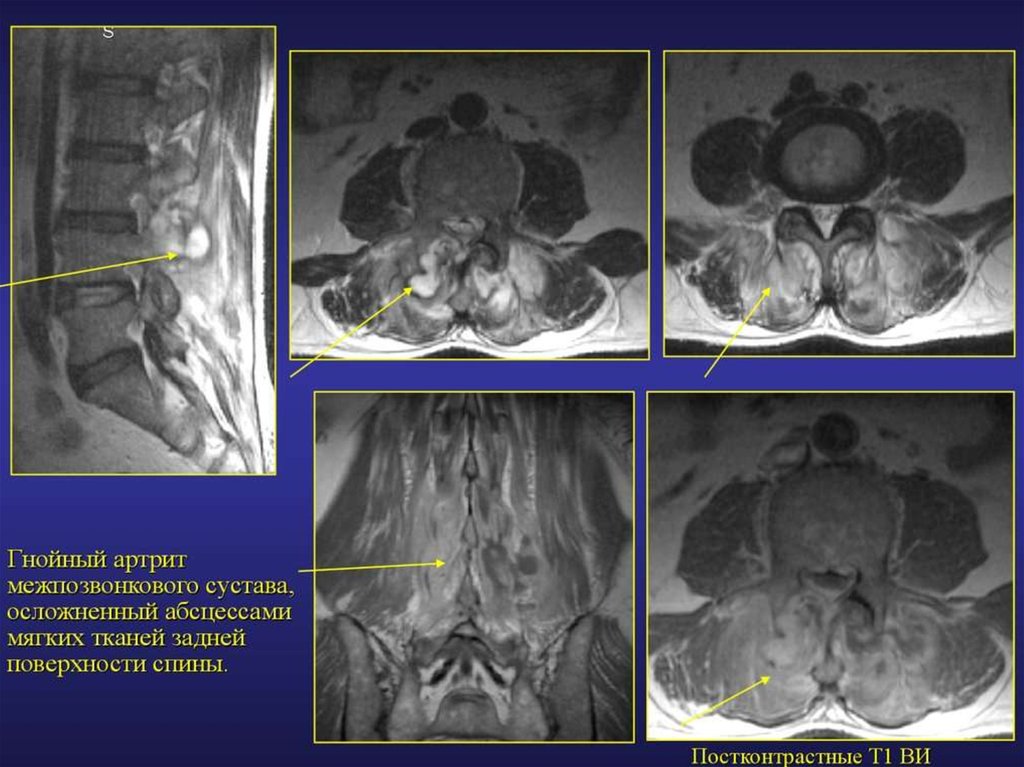

МРТ диагностика повреждений и заболеваний мягких тканей